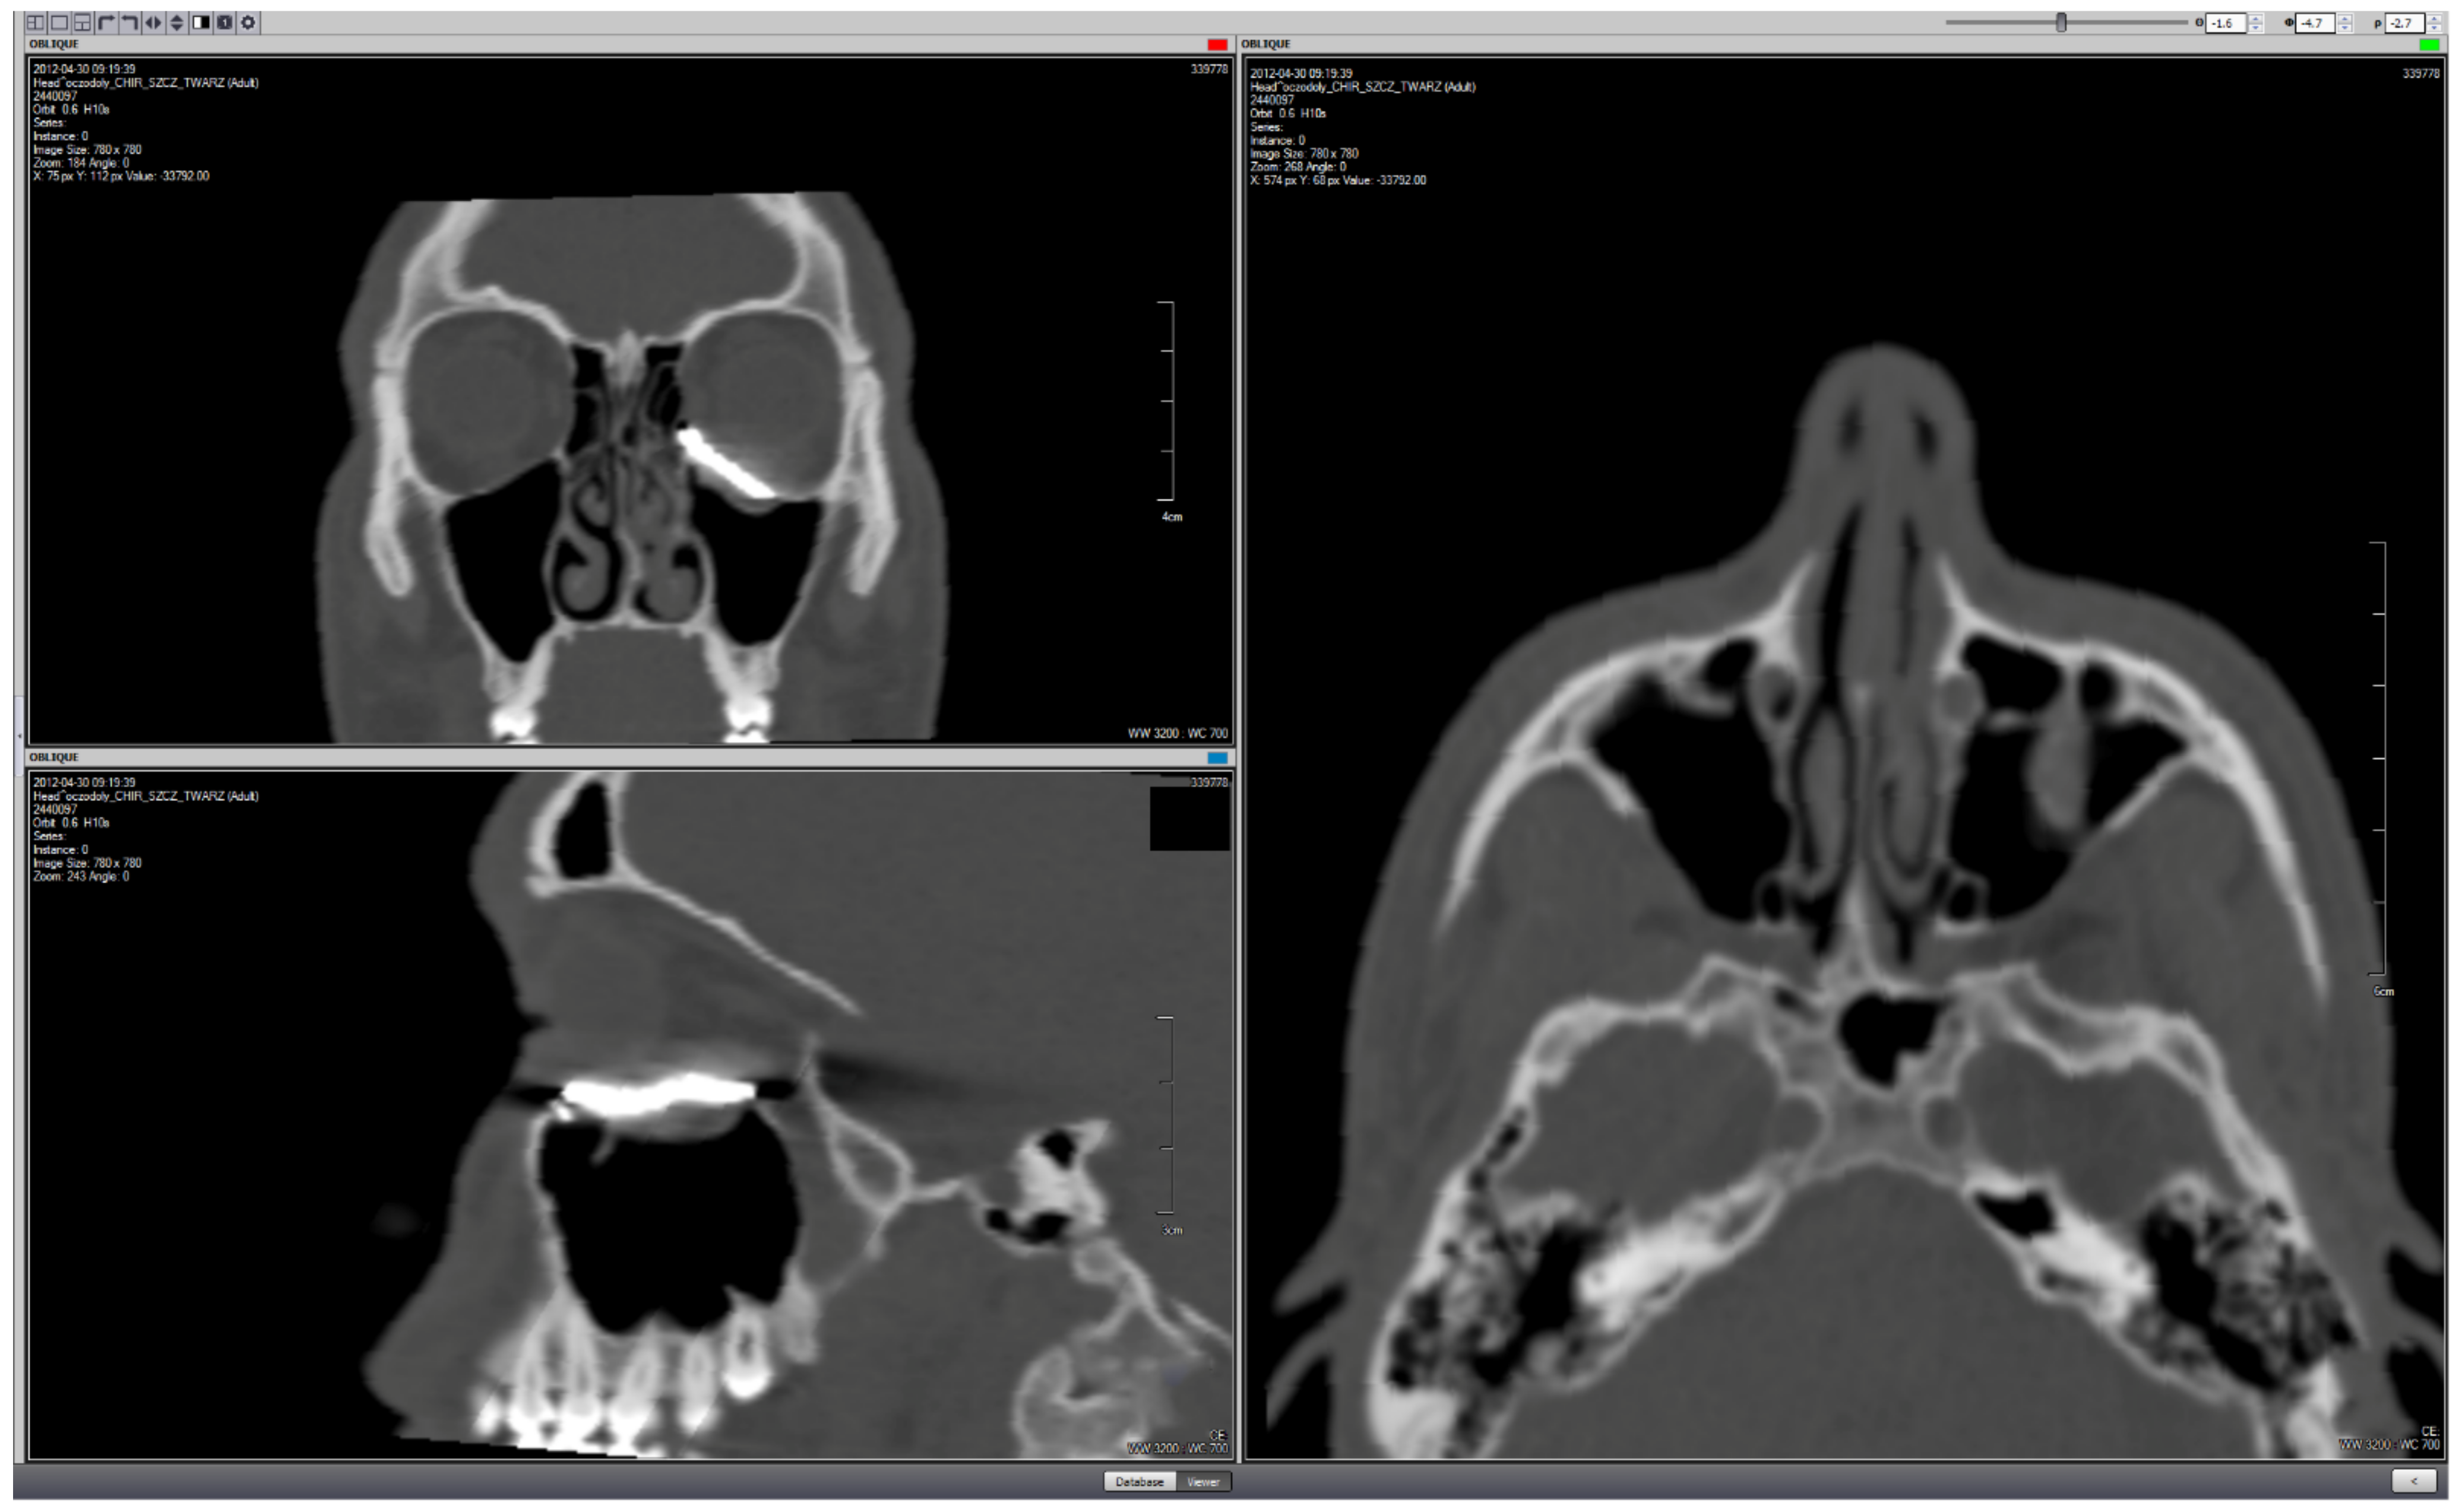

| Case | Sex | Age | ODI | Area of Reconstruction | Approach | Fixing Screws | Follow-Up [Months] | Soft Tissue Shift [mm] | |

|---|---|---|---|---|---|---|---|---|---|

| 1 | M | 19 | 1 | Orbital wall defect | ![]() | Tc | 2 | 99 | 2.01 |

| 2 | F | 22 | 3 | Orbital wall defect | ![]() | Tc | 2 | 98 | 2.58 |

| 3 | M | 23 | 1 | Orbital wall defect | ![]() | Tc | 2 | 96 | 1.98 |

| 4 | M | 32 | 1 | Orbital wall defect | ![]() | Tc | 2 | 94 | 2.13 |

| 5 | F | 20 | 3 | Orbital wall defect | ![]() | Tc | 2 | 90 | 2.96 |

| 6 | M | 21 | 1 | Orbital wall defect | ![]() | Tc | 2 | 89 | 1.27 |

| 7 | M | 24 | 5 | Orbital wall defect | ![]() | Tc | 1 | 73 | 4.00 |

| 8 | M | 27 | 2 | Zygomatic deformation | ![]() | Tm | 1 | 91 | 1.78 |

| 9 | M | 31 | 2 | Zygomatic deformation | ![]() | Tm | 1 | 89 | 6.63 |

| 10 | F | 29 | 2 | Zygomatic deformation | ![]() | Tm | 1 | 88 | 5.42 |

| 11 | M | 46 | 2 | Zygomatic deformation | ![]() | Tm | 1 | 86 | 5.21 |

| 12 | M | 37 | 2 | Zygomatic deformation | ![]() | Tm | 1 | 82 | 5.32 |

| 13 | M | 28 | 7 | Orbital rim and forehead | ![]() | Se | 2 | 82 | 3.89 |

| 14 | M | 24 | 7 | Orbital rim and forehead | ![]() | Sc | 4 | 81 | 7.84 |